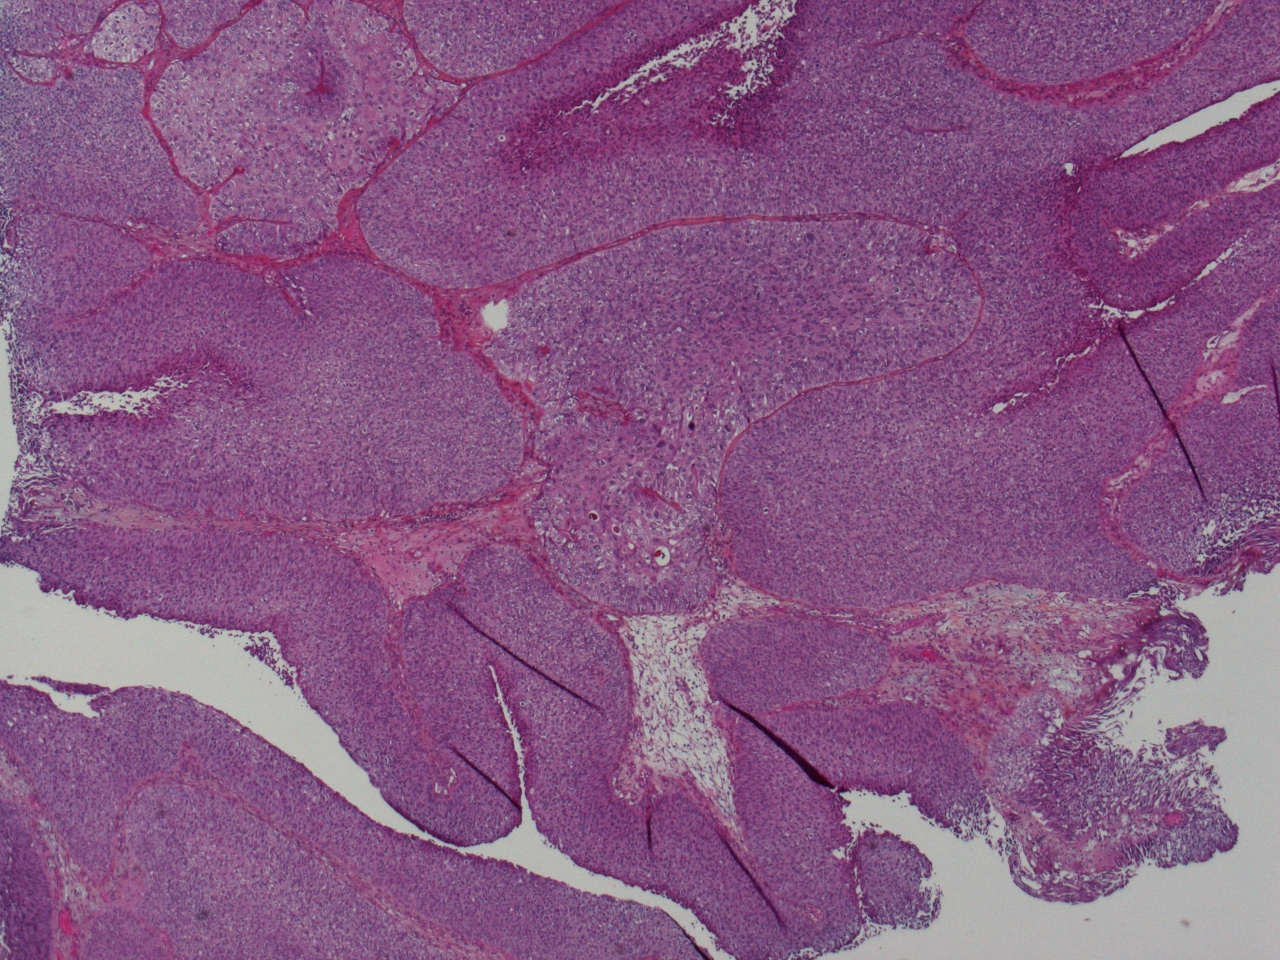

Bladder Papillary Lesions

Case ID: 475